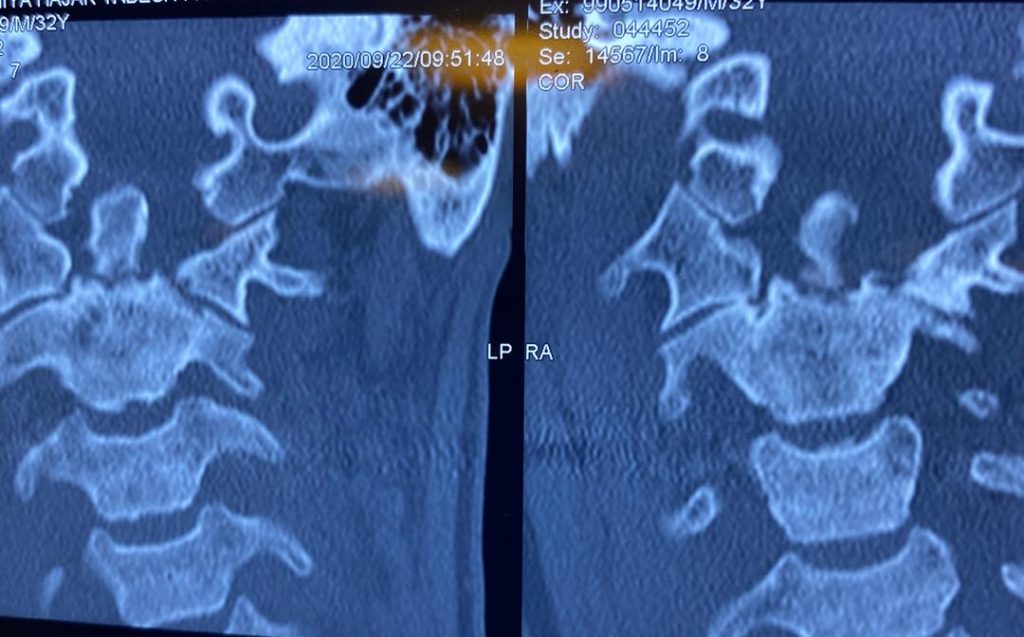

بیمار خانم جوان با سابقه ضربه شدید گردن و شکستگی زائده ادونتویید مهره دوم گردن که تحت عمل جراحی قرار گرفتند. تصاویر قبل و بعد از عمل را در زیر مشاهده می نمایید . همچنین توضیحات دکتر باغبان را در حین جراحی در ویدئوی انتهای مقالات مشاهده کنید. (ویدئو حاوی تصاویر جراحی می باشد)

تصاویر قبل از عمل